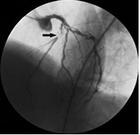

冠状动脉狭窄造影(箭头充盈缺损处为狭窄)